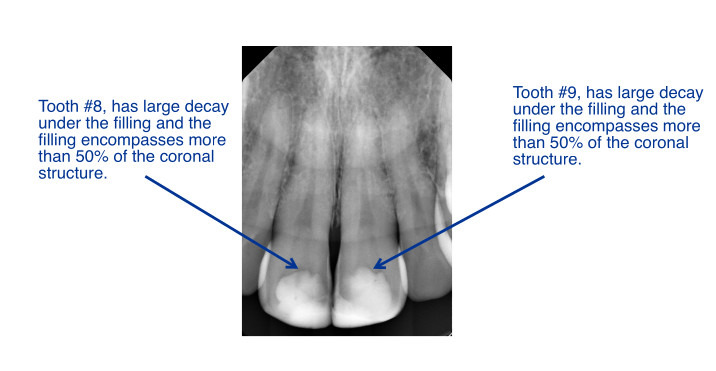

In 2005 I knocked out my two front teeth in a skateboarding accident and had temporary caps put on, which after 20 years, have eroded away, leaving very little of the fake teeth stable. After several visits with a dentist in Northern Virginia I was told that my two front teeth are in a very bad condition and if they are not attended to soon I'm in danger of losing them altogether. This news has been hard to get, especially in recent years as my financial situation has also deteriorated significantly, through no fault of my own, but nonetheless leaving me in a pretty vulnerable situation.

I have been told that if I do not get a root canal on each of my front teeth ($1050 x 2) that my teeth are at risk of abscessing and will need to be extracted. The cost of the new teeth themselves is $3,736, bringing the total to almost $6,000, or roughly half my yearly income at the moment. I am grateful to have been approved for $2,500 through the MusicCares foundation, which will help me out a ton, but still leaves quite a bit of the bill to foot. I've also been told that if I don't act quickly, that the work/teeth implants would amount to about $14,000, making this a particularly time sensitive procedure.